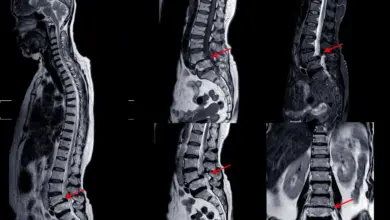

Patologias da Coluna  Cisto facetário da coluna: causas, sintomas e cirurgiaO cisto facetário da coluna é uma bolsa de líquido nas articulações facetárias que pode comprimir nervos e causar dor.… Leia mais »

Patologias da Coluna  Artropatia facetária: sintomas, causas e como tratarA artropatia facetária é uma das causas mais comuns de dor na coluna. O problema começa nas facetas — as… Leia mais »

Patologias da Coluna  L5-S1: tudo sobre a articulação lombossacraA articulação L5-S1 é o ponto de transição entre a coluna lombar e o sacro. Essa região suporta altas cargas,… Leia mais »